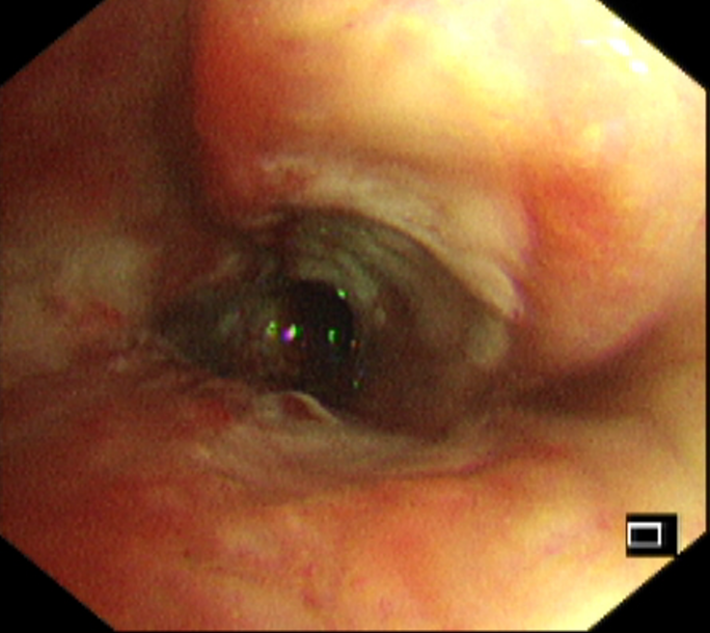

经过多学科讨论,征得患者及其家属同意后,专家团队决定启用“光学活检”的新技术——共聚焦激光显微内镜可视化活检术。术中,专家团队通过激光共聚焦原理,将细胞放大1000倍,对病变组织进行精准取样活检,结合其它检验结果,排除了恶性肿瘤可能,诊断为支气管结核,直接为卢女士实施了气道内冷冻治疗。

共聚焦显微镜下见到大量炎性细胞